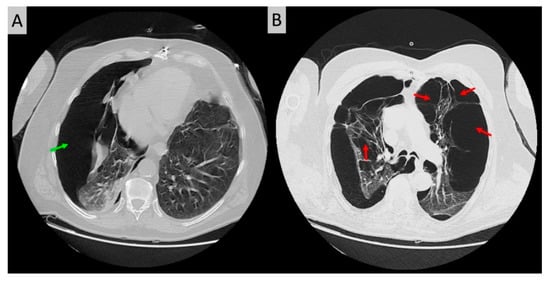

2.3. Diagnostic Assessment and Therapeutic Intervention

2.4. Final Diagnosis